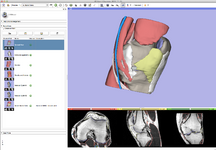

The community of Slicer developers is proud to announce the release of Slicer 4.0.

- Slicer 4.0 includes a major overhaul of the user interface, improved and simplified workflows for major tasks, simplified procedures for developers, and improved Python support.

Slicer is a community platform created for the purpose of subject specific image analysis and visualization.

- Multi-modality imaging including, MRI, CT, US, nuclear medicine, and microscopy

- Multi organ from head to toe

- Slicer 4.0 - New and Improved Modules